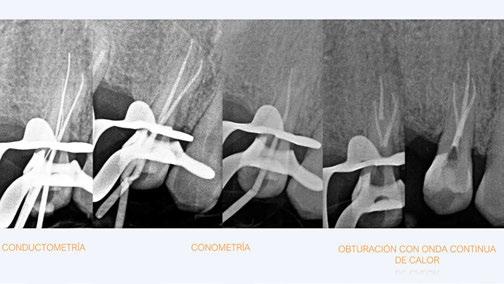

Debido a la gran curvatura que se produce en la bifurcación, tenemos que precurvar los instrumentos manuales y rotatorios, para facilitar que los instrumentos alcancen la LT (Figura 11). Terminamos el conducto mesiovestibular y palatino en conicidad .06 y el disto-vestibular en .04 debido al riesgo que pensamos que correríamos si hacemos una secuencia más amplia.

Valorando cada uno de los factores que hemos descrito anteriormente, podemos decidir, para el éxito de este tratamiento, una combinación: secuencia más progresiva; trabajar 3 ciclos por conducto para los instrumentos de preinstrumentación y conformación; eliminación de interferencias coronales con puntas ultrasónicas

e instrumento 25.09; terminar en conicidad .04/.06 según la dificultad del conducto; combinar movimiento continuo y alterno; y usar instrumentos precurvados de manera manual previo al rotatorio. Todo esto hará que resolvamos este caso clínico de manera satisfactoria (Figura 12). ●

Figura 10. Estudio Radiográfico en 2D y 3D del caso clínico. Figura 11. Secuencia operatoria que realizamos en cada uno de los conductos. Figura 12. Secuencia realizada para la obturación con onda continua.